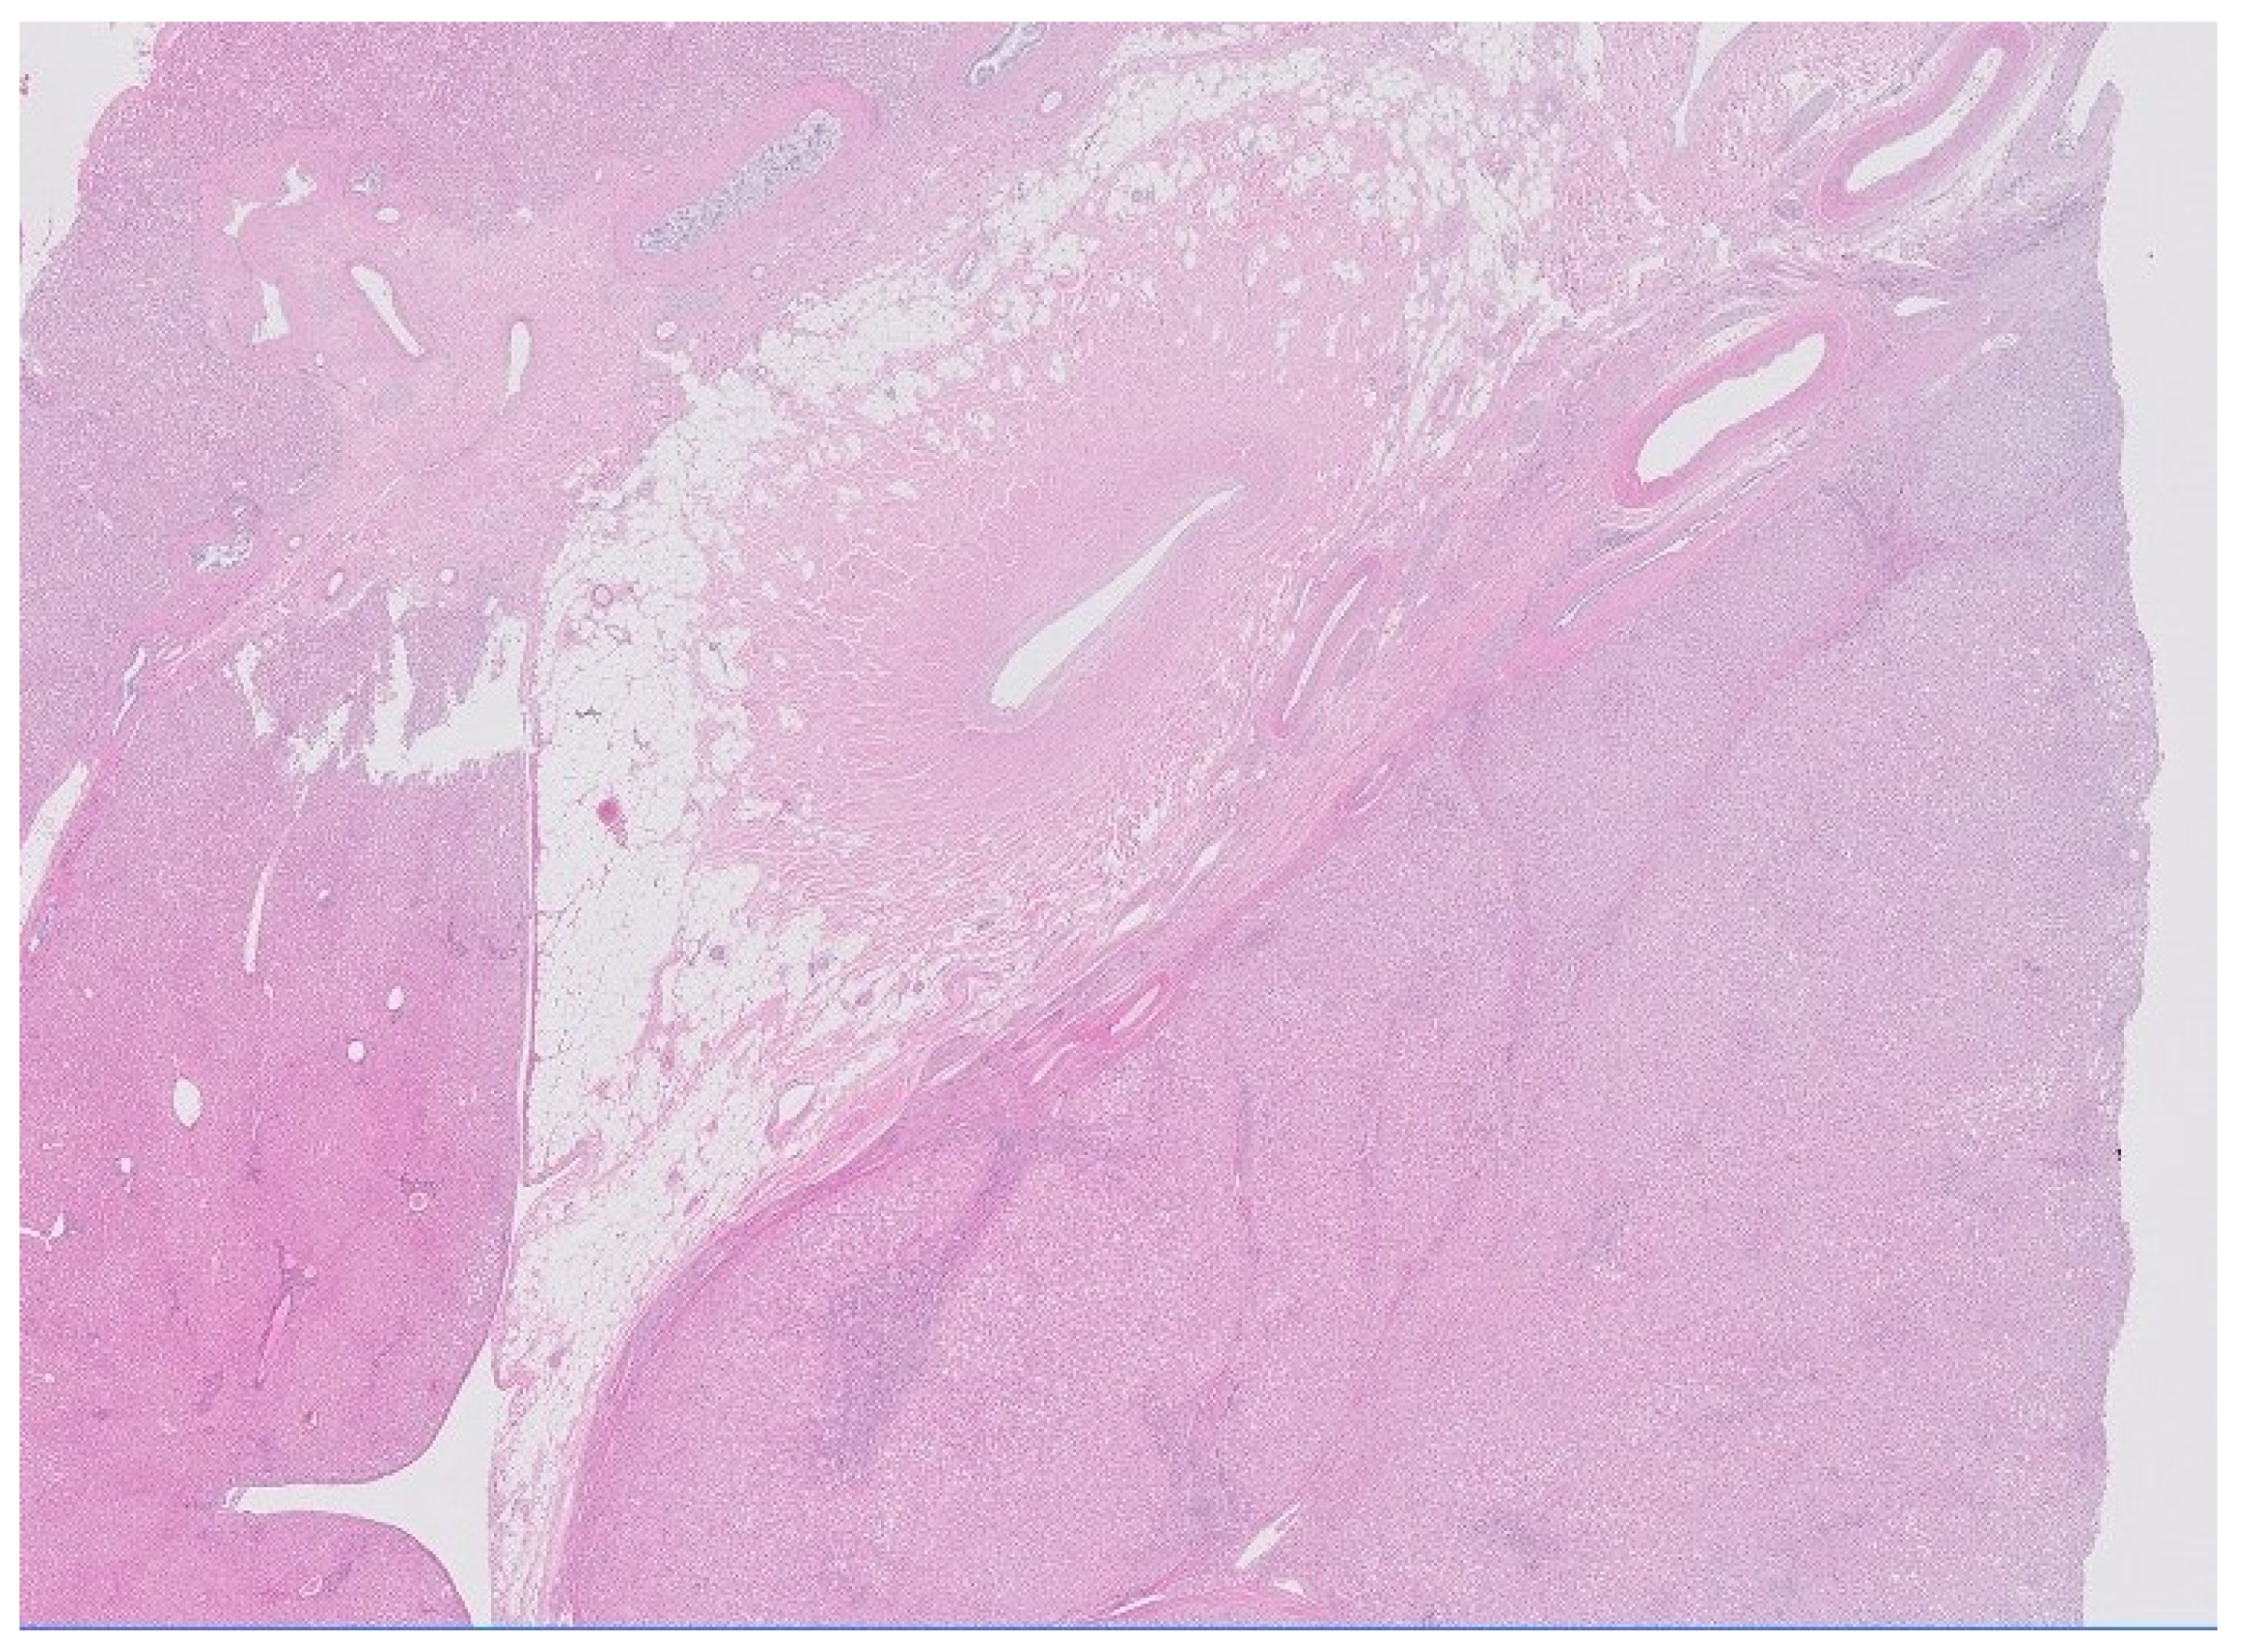

Differential Diagnosis of Hepatic Mass with Central Scar: Focal Nodular Hyperplasia Mimicking Fibrolamellar Hepatocellular Carcinoma

2. Case Report